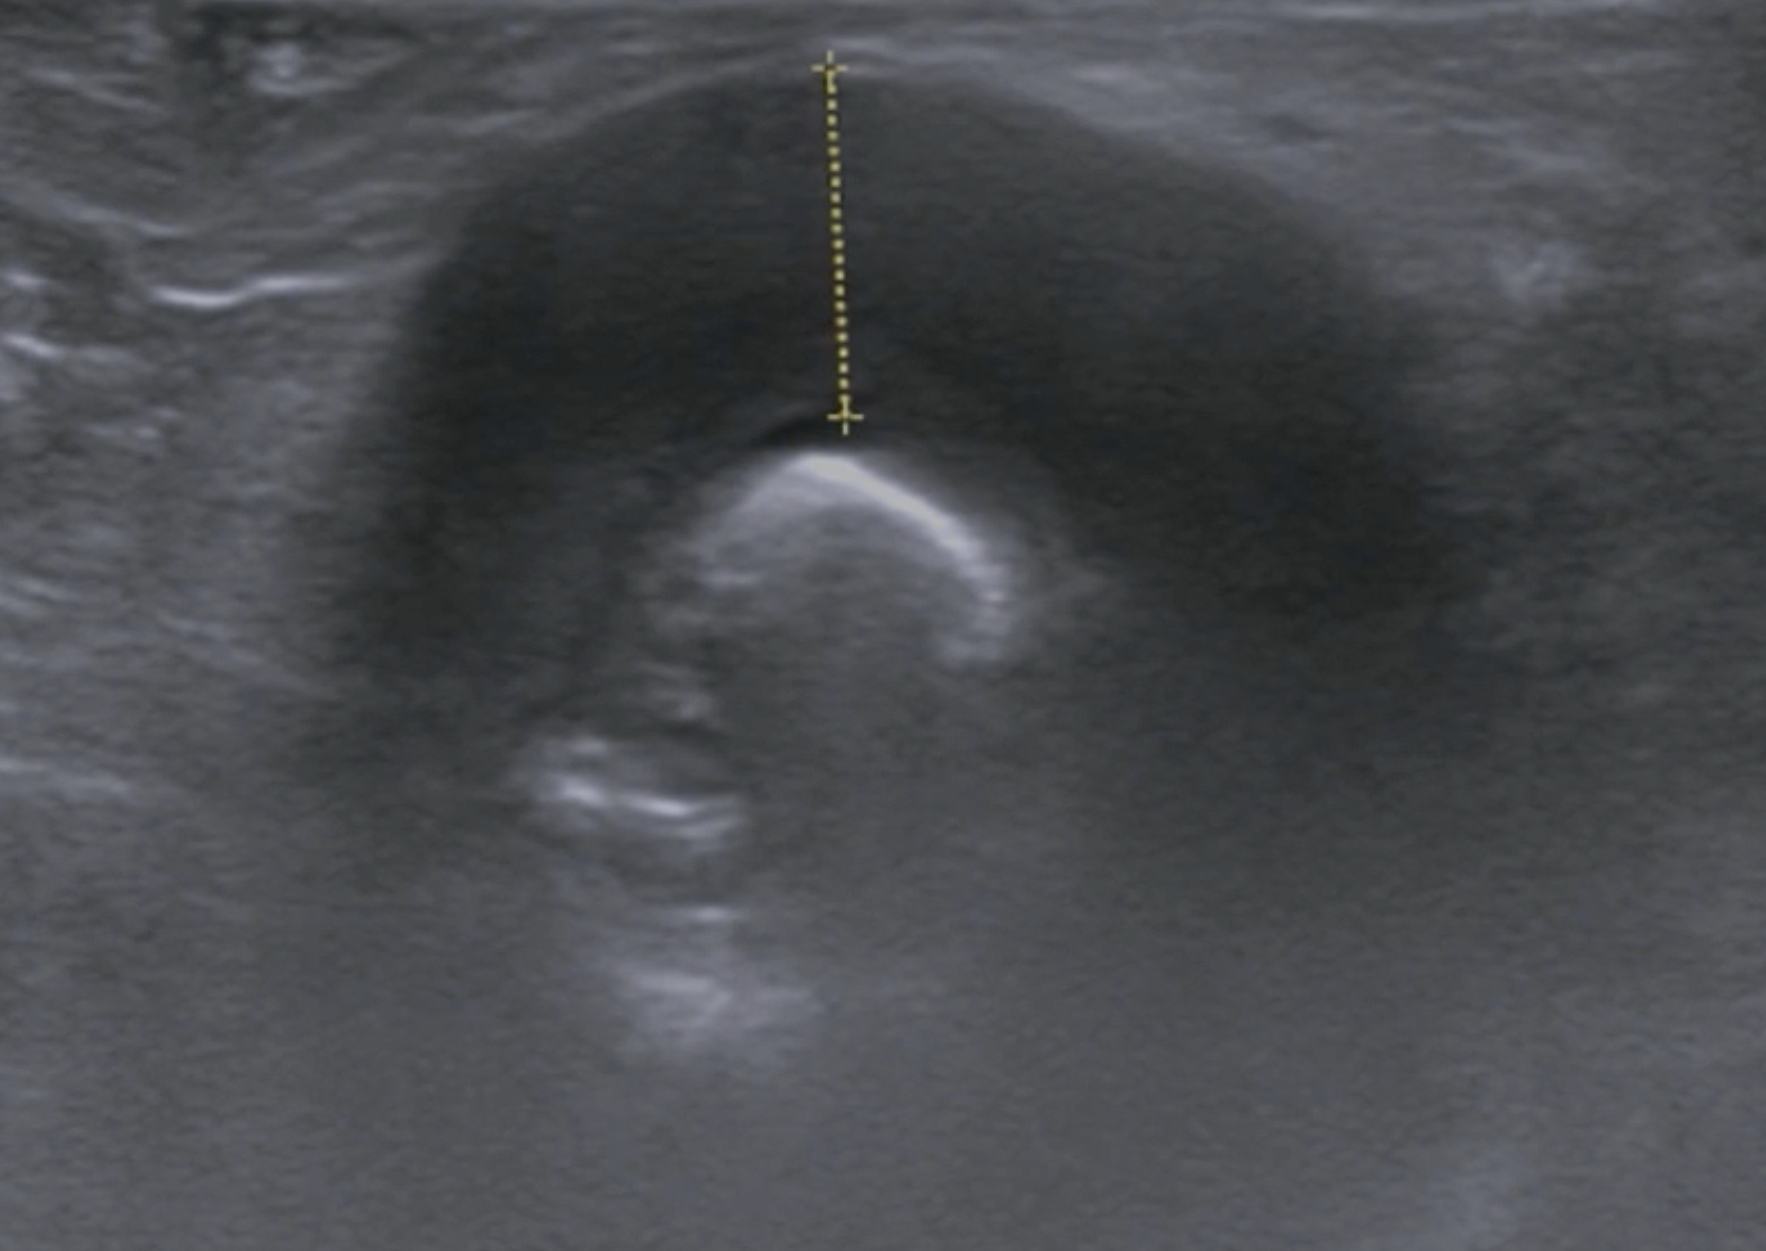

L'hématémèse et la méléna sont indicatives de saignements gastriques et / ou petits intestinaux, bien que les saignements occultes ne puissent être détectés que par des changements à l'examen hématologique suggérant une carence en fer. Les investigations incluent ensuite l'imagerie et l'endoscopie gastro-intestinale supérieure, mais les lésions au-delà de la portée de l'endoscope ne peuvent être identifiées que par endoscopie par vidéocapsule ou lors de la laparotomie. Du sang frais en présence d'une consistance normale des selles (hématochezia) indique un saignement colique focal. Souvent, une masse hémorragique est palpable à l'examen rectal numérique, mais une coloscopie peut être nécessaire.